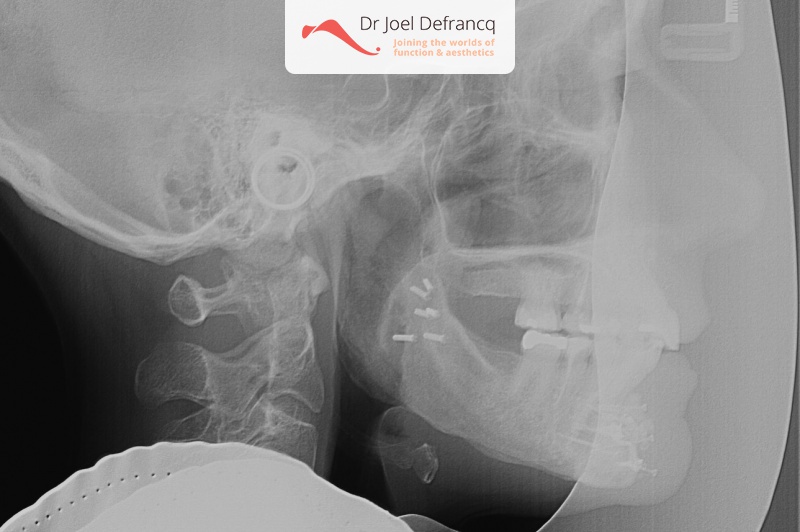

- Te kleine onderkaak (Overbeet)

- Diepe beet, vierkant gezicht

Kaakchirurgie

- Verlenging onderkaak (BSSO)

- Kinchirurgie

- Onderrand shaving der onderkaak